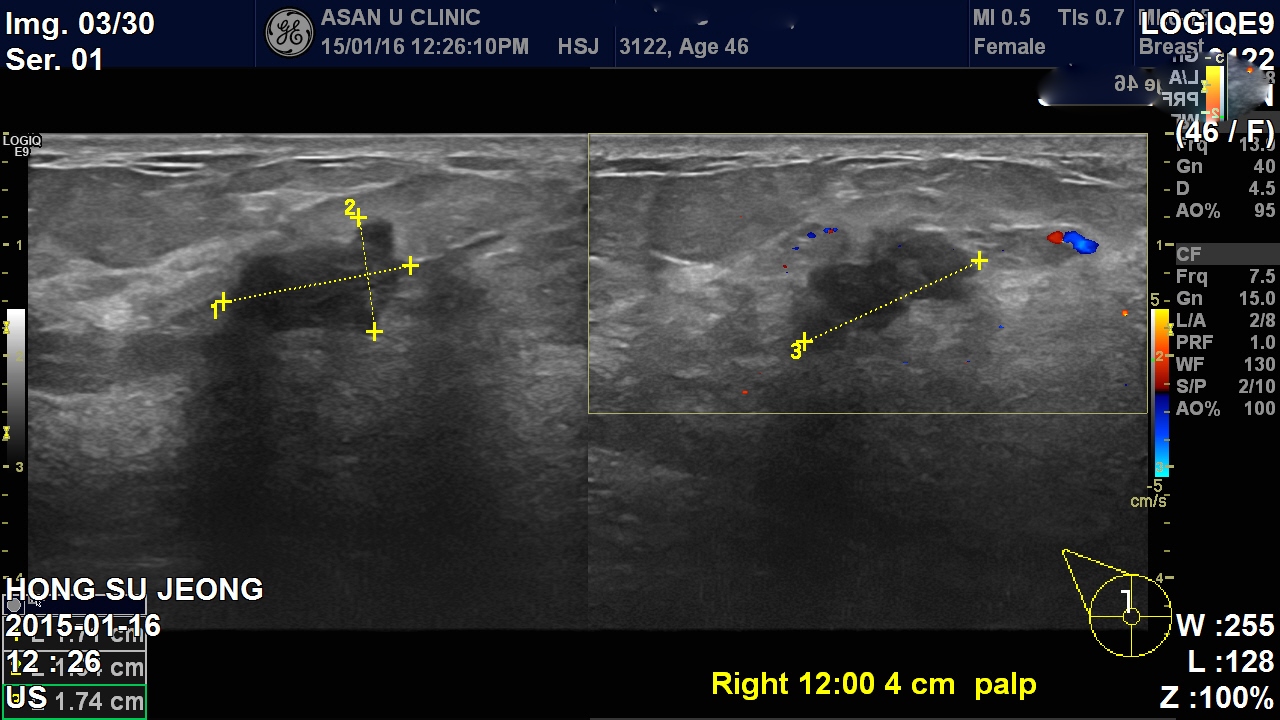

두달전부터 만져지는 우측 유방에 몽오리로 내원한 46세 여성분입니다.

본원 초음파상 우측에 만져지는 혹 근처에 여러개의 혹이 더 있었고

겨드랑이 림프절도 비대한 상태였습니다.

반대쪽 유방에도 혹이있어 양쪽 유방의 암의심 종괴와 우측 겨드랑이 림프절의 세침 검사를 진행하였고, 안타깝게도 양측 유방에 혹과 겨드랑이 림프절 모두가

유방의 침윤성 소엽암으로 진단되어

우측유방의 유방암과 림프절 전이, 좌측 유방의 유방암(액와림프절 전이 없음) 보였습니다.